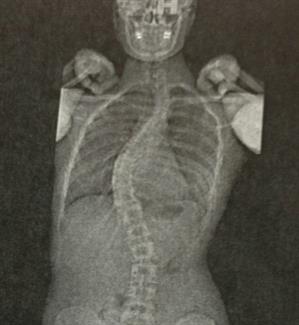

A routine physical in fall 2009 revealed a severe lateral curvature in the spine of fifth-grader Hannah Martinez. At 11 years old, she was diagnosed with scoliosis. Her parents immediately started praying for God to heal their daughter.

In the following three years, Hannah strapped on a back brace to combat and stabilize the 32-degree curve in her spine. She’d only remove the brace for small increments of time, like during sports practices or showering. When the growth plates settled into place following eighth grade, Hannah’s brace-wearing days were behind her, but while most people with scoliosis go on to have no further issues, each X-ray at Hannah’s yearly checkups showed her spine continually getting worse.

Doctors typically recommend surgery at a 50-degree curve. Hannah’s was 54.

Perhaps the most frightening threat, though, was her diminished lung volume. Hannah was only at 70-percent breathing capacity due to her spine lying upon one of her lungs.